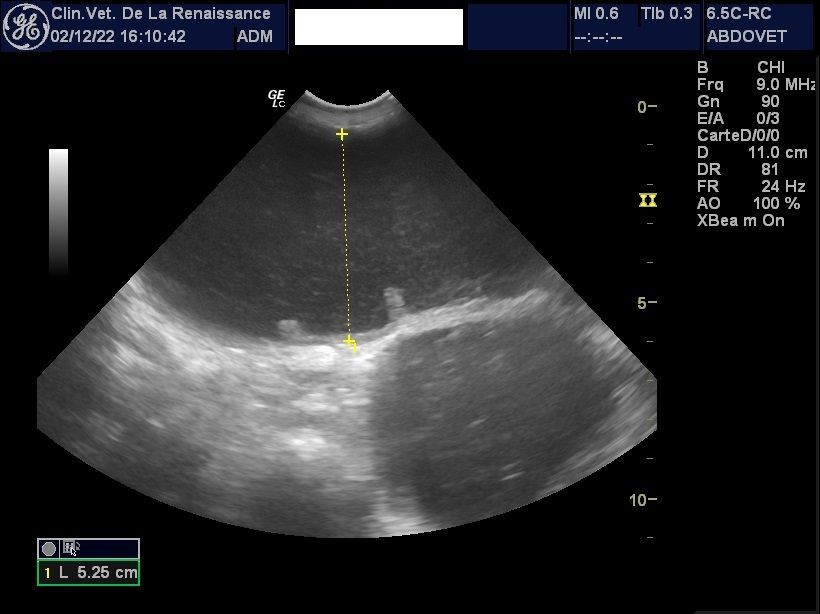

L'échographie

La clinique est équipée d'un échographe pour l'exploration de la cavité abdominale et de ses organes. Nous pouvons réaliser une échographie ciblée sur un organe ou sur l'ensemble des organes abdominaux, dans le cadre d'un diagnostic ou le suivi d'une pathologie ou d'une gestation. Un doppler permet dans le cadre de la gestation de mesurer la fréquence cardiaque des chiots. L'échographie peut être réalisée avec ou sans anesthésie générale en fonction de l'animal.